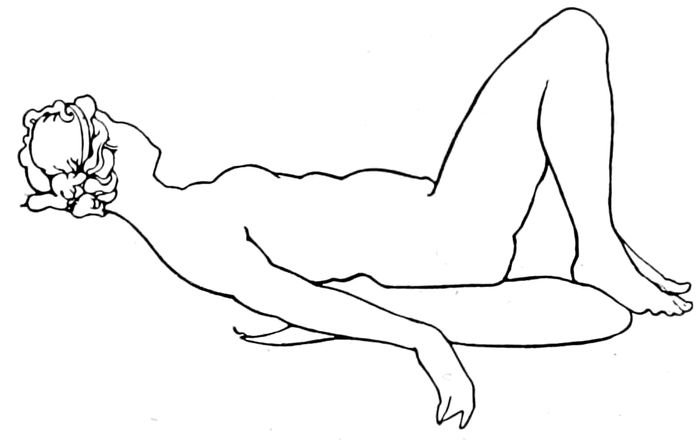

| 107. |

The Sims position |

241 |

| |